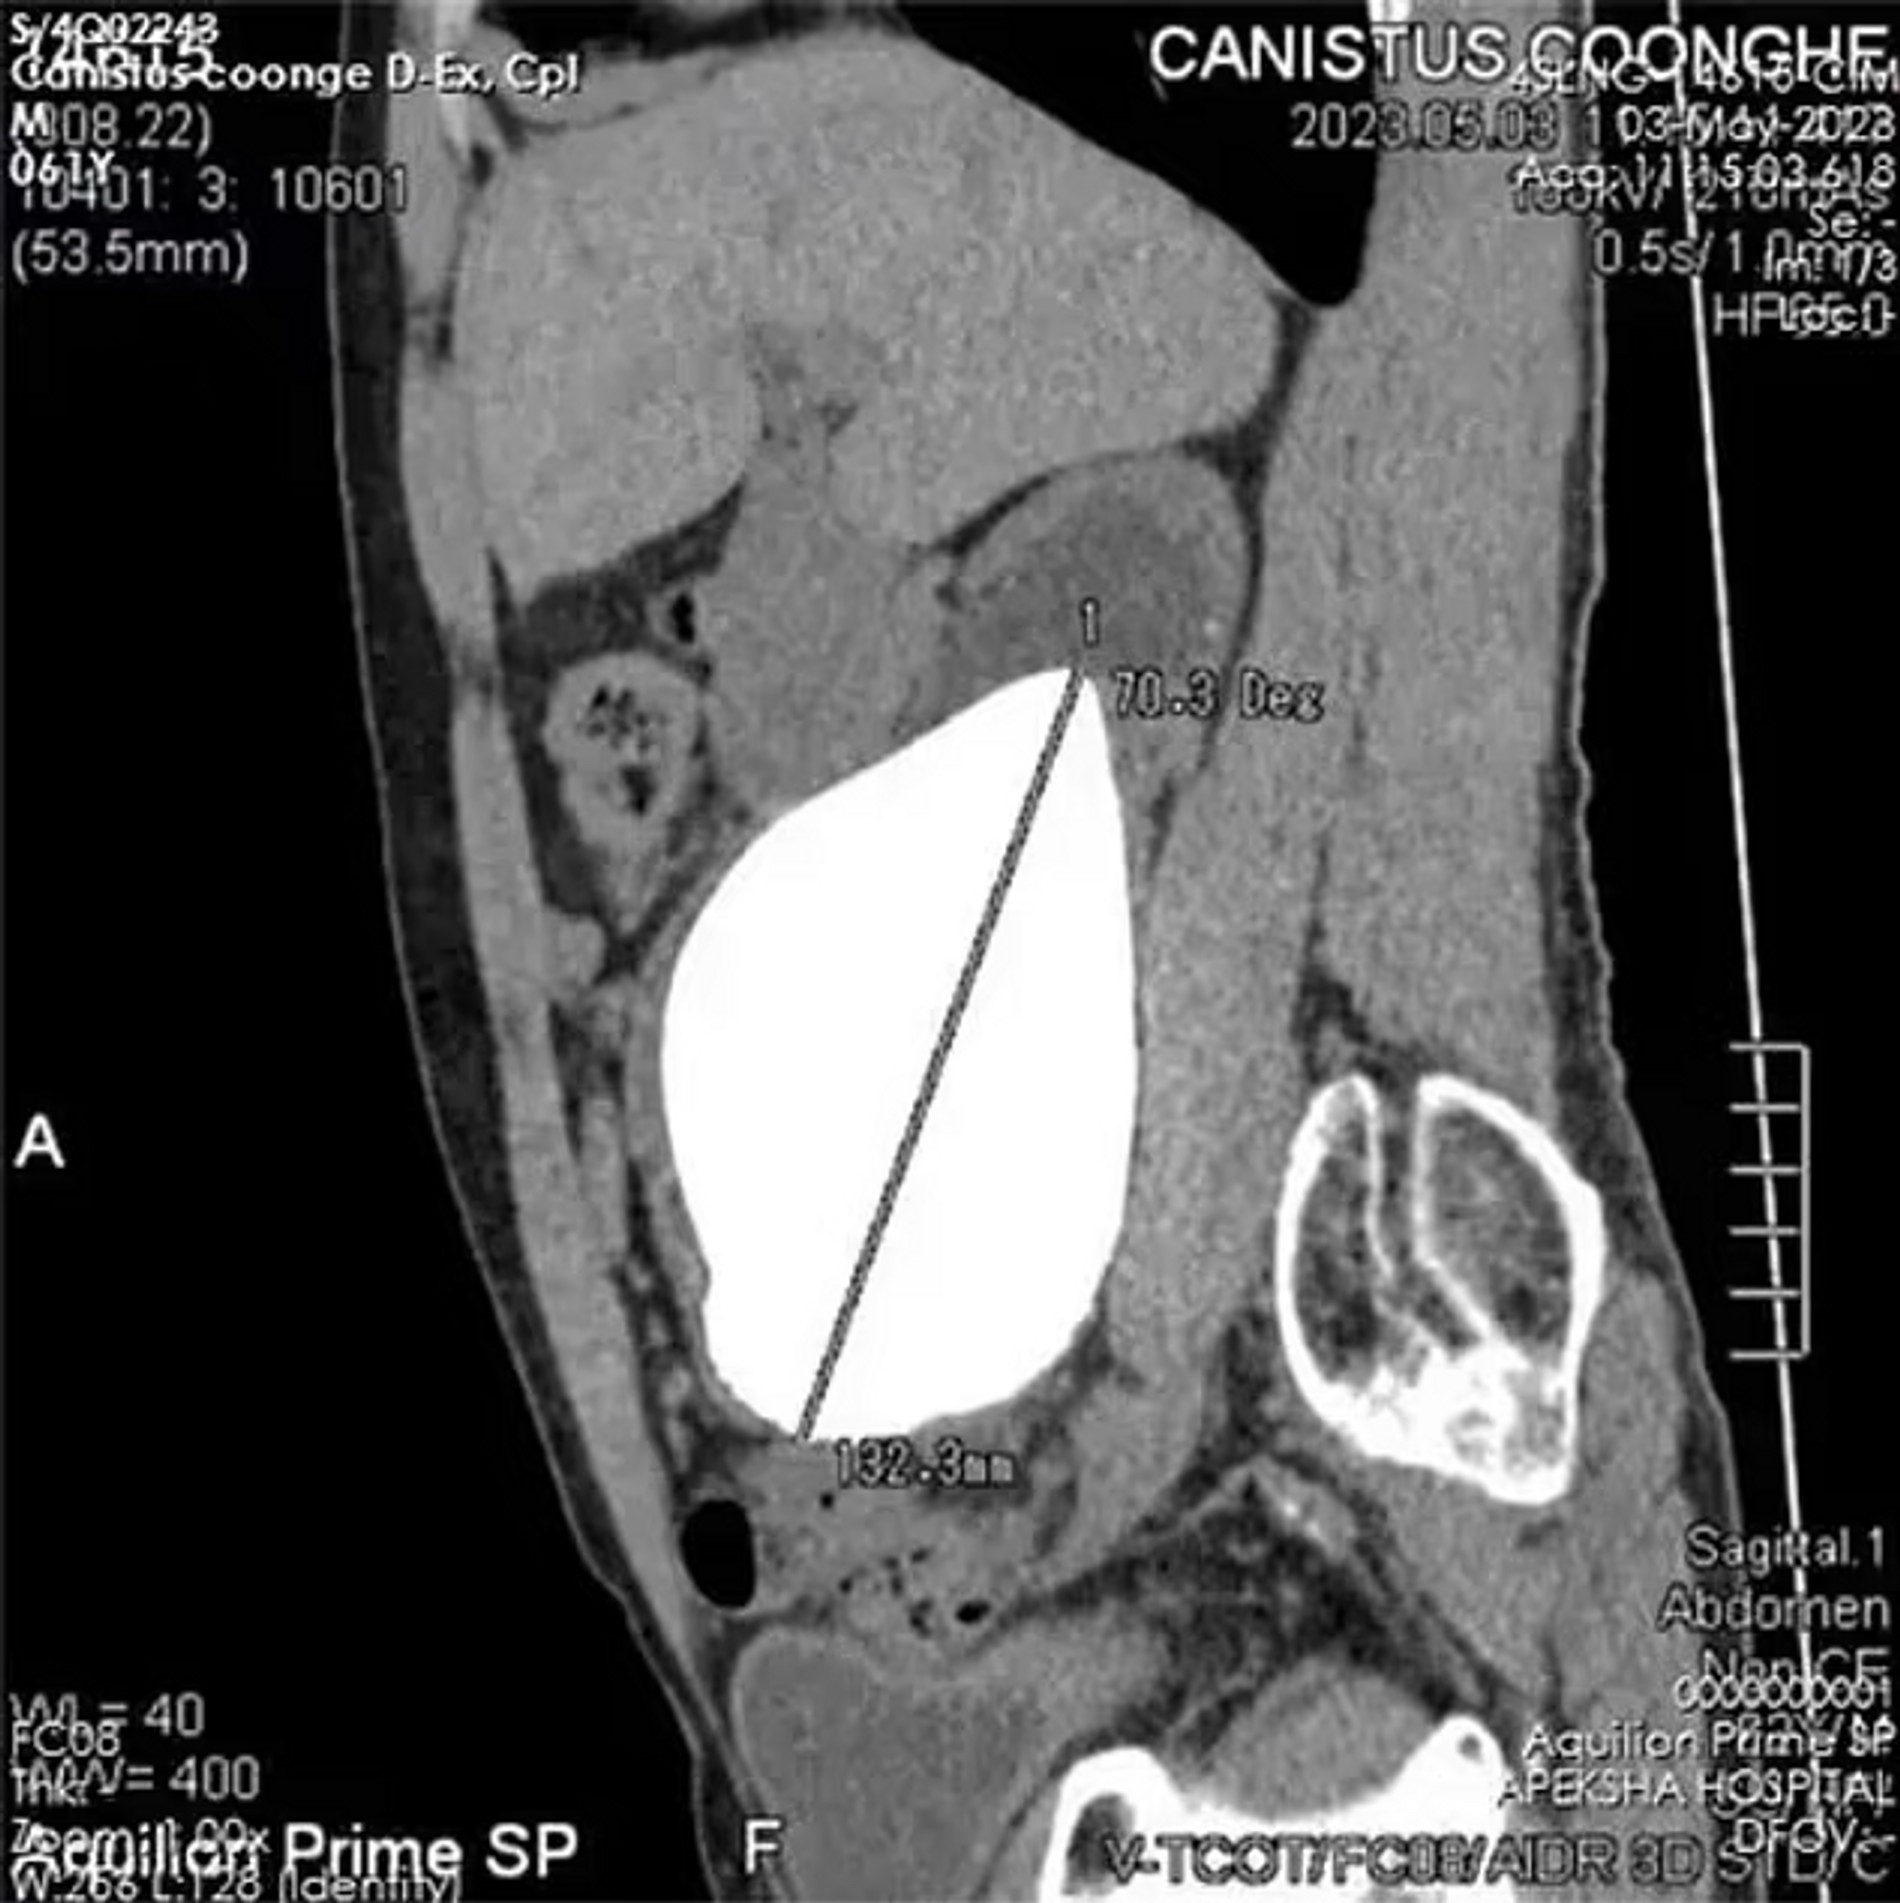

Не знали, что Книга рекордов Гиннесса отслеживает такие достижения? Мы тоже. Как пишет издание Daily Mail, список самых-самых в этой сомнительной номинации возглавил гражданин Шри-Ланки — отставной военный Канистус Кунхе. Камень, выросший в правой почке 62-летнего мужчины, имел длину 13,37 см и ширину 10,55 см, но, что удивительно, никак не влиял на работу внутренних органов. Еще удивительнее то, что этот рекордсмен весом аж в 800 грамм не причинял пациенту никакого дискомфорта — а ведь порой даже самые маленькие камни становятся причиной жуткой боли.